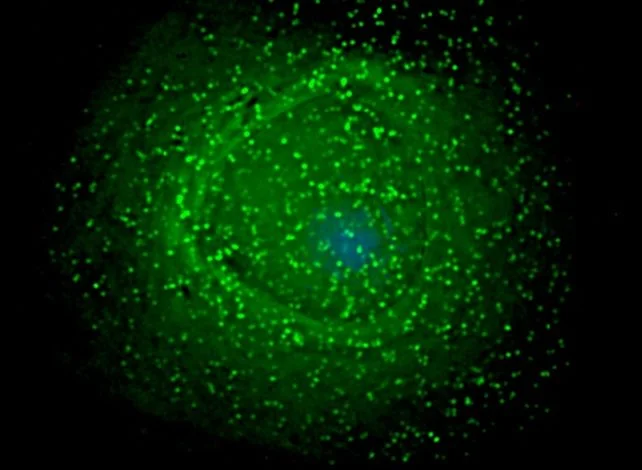

Ученые раскрыли одну из ключевых уловок вируса иммунодефицита человека (ВИЧ), которая позволяет ему десятилетиями скрываться в организме. Новое исследование проливает свет на то, где и как ВИЧ формирует свои латентные резервуары, что является важным шагом в поиске способов полного избавления пациентов от вируса. В своей скрытой стадии ВИЧ может существовать внутри определенных клеток-хозяев в виде дремлющего «провируса» — вирусного генома, встроенного в ДНК клетки человека. Именно это делает вирус таким трудным для уничтожения, даже когда современная антиретровирусная терапия подавляет его размножение и останавливает развитие болезни, но не может атаковать спрятанные провирусы.

Ранее было известно, что ВИЧ сохраняется в различных тканях, включая мозг, почки, печень, легкие и желудочно-кишечный тракт. Основным резервуаром являются Т-хелперы иммунной системы, но вирус также прячется в клетках кожи, белых кровяных тельцах и специфичных для органов клетках. Многие детали этого процесса оставались неясными. Согласно новому исследованию, ВИЧ использует тканеспецифичный подход, маскируясь в ДНК клетки-хозяина и адаптируя свое поведение в зависимости от окружения. Например, в мозге он избегает активных генов и скрывается в менее активных регионах ДНК.